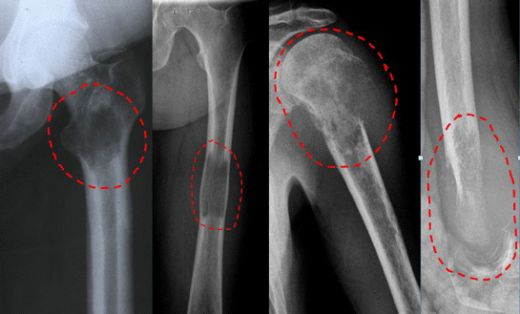

Kemik Kistinin Tanısı Kemik kistinin tanısı genellikle aşağıdaki yöntemlerle konulmaktadır: